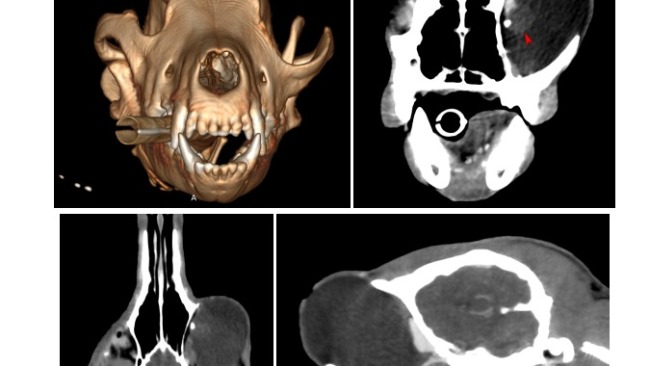

Uma bardzo cierpi, więc operacja jest niezbędna i musi być wykonana jak najszybciej. Oba oczka muszą być usunięte. W jednym z nich dodatkowo jest duża narośl od środka, prawdopodobnie polip, który będzie usunięty wraz z oczkiem. Koszt operacji obu oczu plus wizyty kontrolne i leki to kwota 5 tyś.